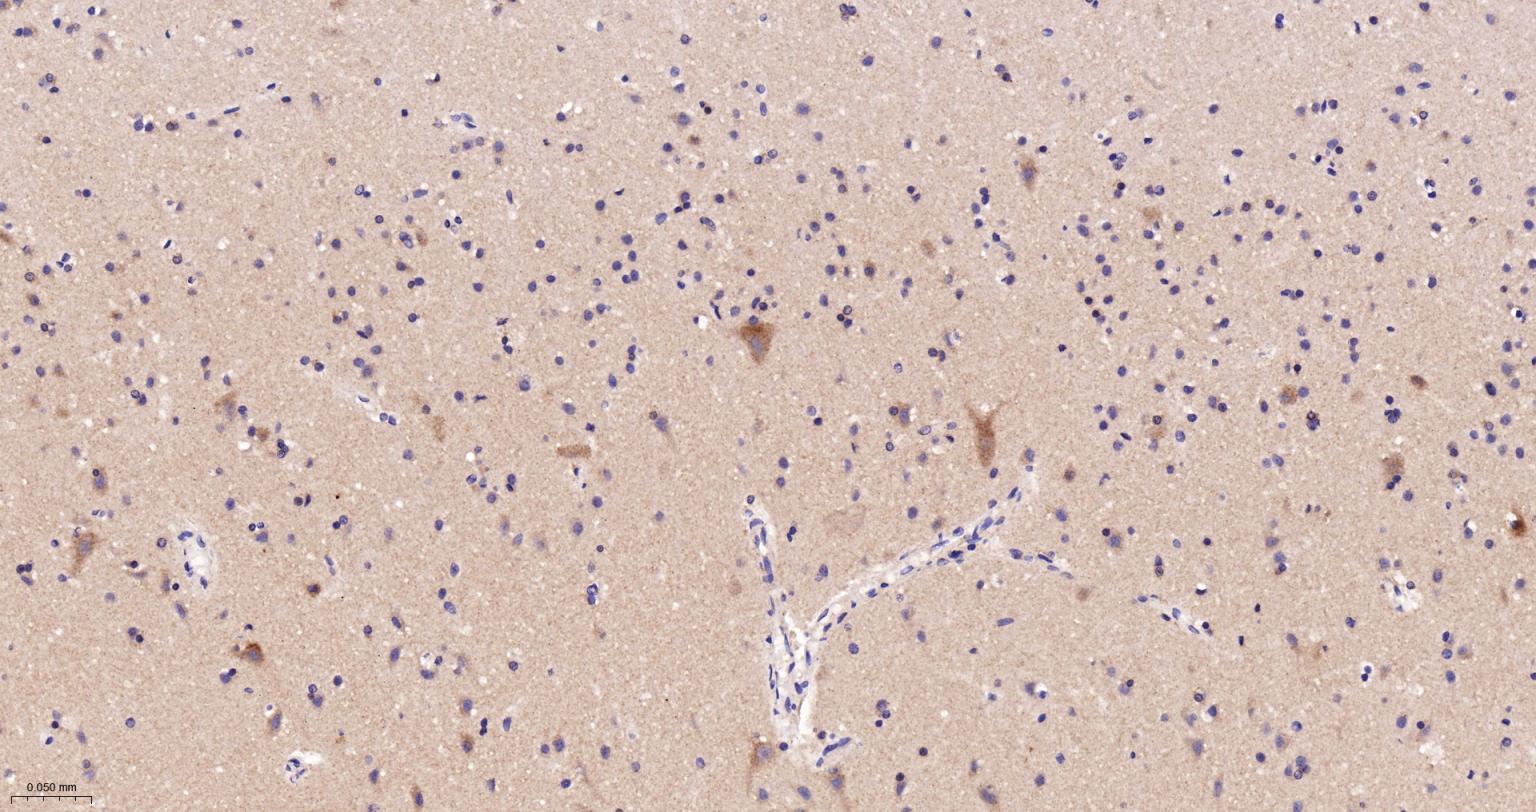

Paraformaldehyde-fixed, paraffin embedded Human Cerebrum; Antigen retrieval by boiling in sodium citrate buffer (pH6.0) for 15 min; The section was incubated with ATP5MC1 Monoclonal Antibody, Unconjugated (bsm-61256R) at 1:200 overnight at 4°C, followed by conjugation to the bs-0295G-HRP and DAB (C-0010) staining.